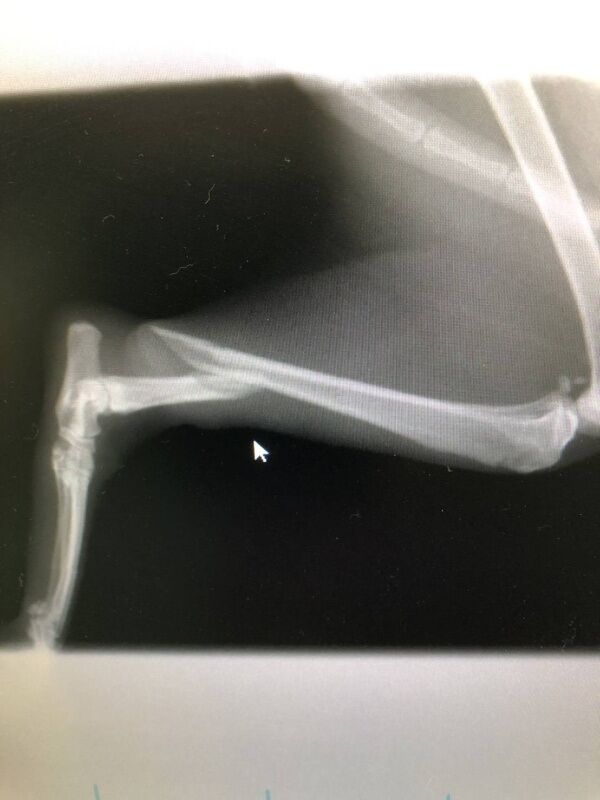

大腿骨ではなく

脛骨の骨折でした。

えへっ・・・

早速

増田院長に

ピンニング手術をしてもらい

お昼すぎに

うちに戻って来ました。

テーピングを

巻き変えているとこです。

猫は暴れさせないように

必要以上に

ガッチリ保定すると

心臓が止まる事があるので

保定する際は

神経を使います。